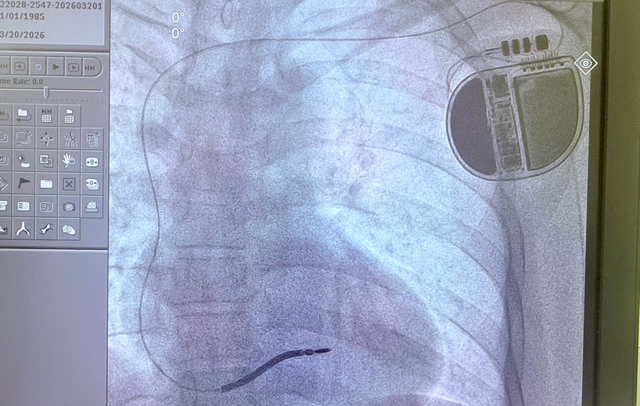

Ảnh chụp kỹ thuật cao cho thấy máy phá rung tim tự động cấy an toàn vào người anh H. Ảnh: BVCC.

Sau hội chẩn, các bác sĩ quyết định thực hiện cấy máy phá rung tim tự động (ICD) – phương pháp hiệu quả nhất hiện nay để phòng ngừa đột tử ở bệnh nhân nguy cơ cao.

Thiết bị ICD có khả năng theo dõi nhịp tim liên tục, phát hiện sớm các cơn loạn nhịp nguy hiểm và tự động phát xung điện để đưa nhịp tim trở lại bình thường, qua đó ngăn ngừa đột tử.